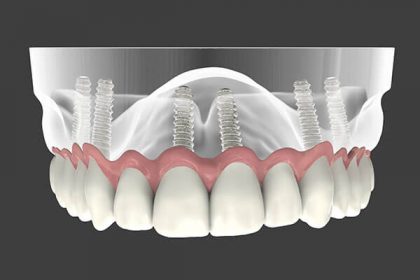

همانطور که می دانید ایمپلنت دندان در یک جلسه انجام می شود و به عنوان جایگزین دندان های از دست رفته می باشد . که پیچی به جنس تیتانیوم داخل استخوان فک به طریق بی حسی موضعی قرار می گیرد و سپس تاج دندان بر روی آن نصب شده و مانند دندان شخص جلوه داده شده و کارکرد دارد ایمپلنت هر دندانی که از دست رفته باشد را پوشش میدهد و قابلیت پوشش یک دندان الی کلیه دندان ها را در بر دارد.

ایمپلنت دندان جلو از اهمیت بسیار بالایی بر خوردار است و نقش حیاتی را ایفا می کند ، زیرا زیبایی دست رفته افراد را به طور طبیعی وتضمینی باز می گردانند . برای ایمپلنت دندان جلویی افراد باید توسط دندانپزشک مورد برسی قرار گیرد تا پارامتر های لازم جهت زیبایی برسی گردد و بافت نگهدارنده ی ایمپلنت به گونه ایی انتخاب گردد که تا آخر عمر سلامت و حجم کافی خود را حفظ کند ، در ایمپلنت دندان جلو زیبایی اطراف ایمپلنت ، سلامت لثه ها ، سلامت دندان های مجاور از اهمیت خاصی بر خور دار است ، به این صورت در انجام آن باید دقت خاصی قائل بود.

این نوع ایمپلنت دندان کاملا دائمی بوده با توجه به این که دندان جلو در معرض آسیب بیشتری قرار می گیرد مقاومت بسیار بالاتری را دارد و اصلا شکسته نمی شود ، از دیگر مزایای ایمپلنت دندان مدت زمان ایمپلنت دندان می باشد که معمولا در دو الی سه جلسه انجام می شود همچنین ایمپلنت دندان زیبایی بخشی آن می باشد زیرا کاملا جلوه ایی طبیعی دارد و زیبایی طبیعی را به افراد هدیه می دهد و چون بیشتر در معرض دید است زیبایی درآن بیشتر اهمیت دارد همچنین این ایمپلنت قابلیت ترمیم شدن را دارد که اگر یک در صد تاج دندان دچار آسیب گردد امکان ترمیم ، جدا سازی و نصب دوباره تاج دندان بر آن را دارد.